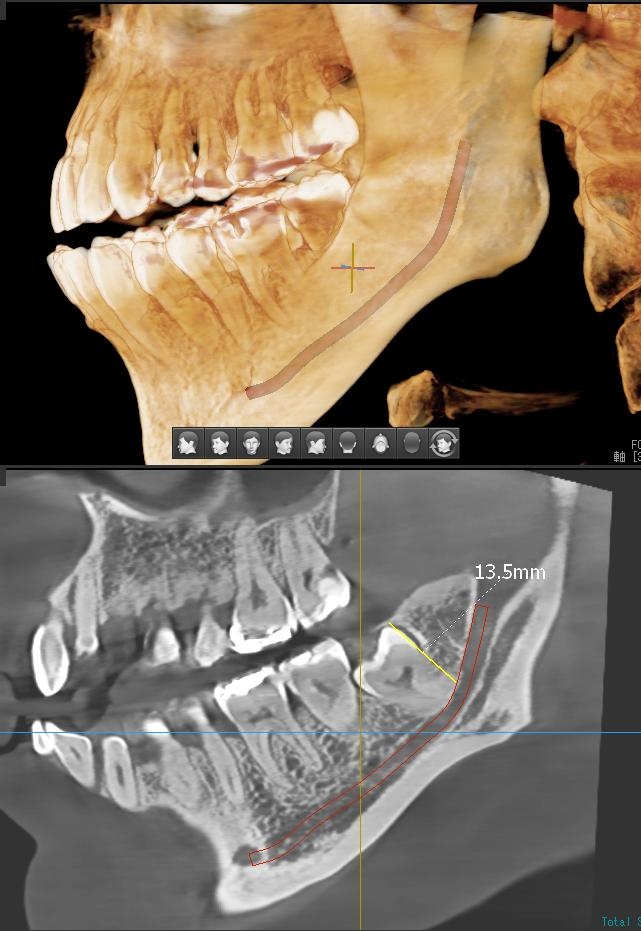

さらに、下顎の親知らずは下歯槽神経に非常に近いところに生えている場合もあるため、CTも撮影し詳しい解析を行います。

親知らずが生えている位置が、神経に近い、あるいは神経に当たっている場合は、大きな病院に紹介する場合もあります。

親知らずの根っこは下歯槽神経から近い距離にありますが、抜歯は可能との診断でした。